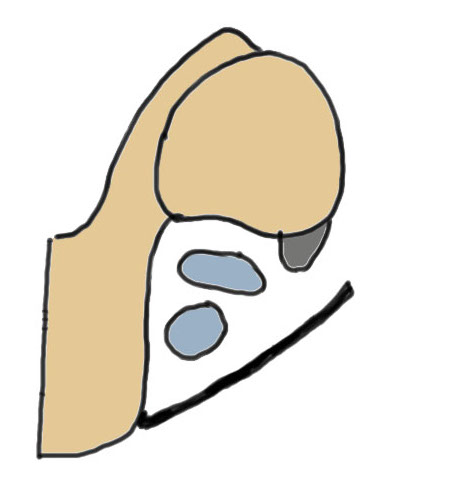

1. Injury to superior peroneal retinaculum (SPR) / fibrocartilaginous ridge (FCR)

Peroneal tendons sublux out of grove

Eckert Classification

| Type 1 | Type 2 | Type 3 | Type 4 |

|---|---|---|---|

| SPR detaches from FCR | SPR and FCR detached | Bony avulsion of SPR and FCR | Midsubstance rupture of SCR |

| 51% | 33% | 13% | ? |